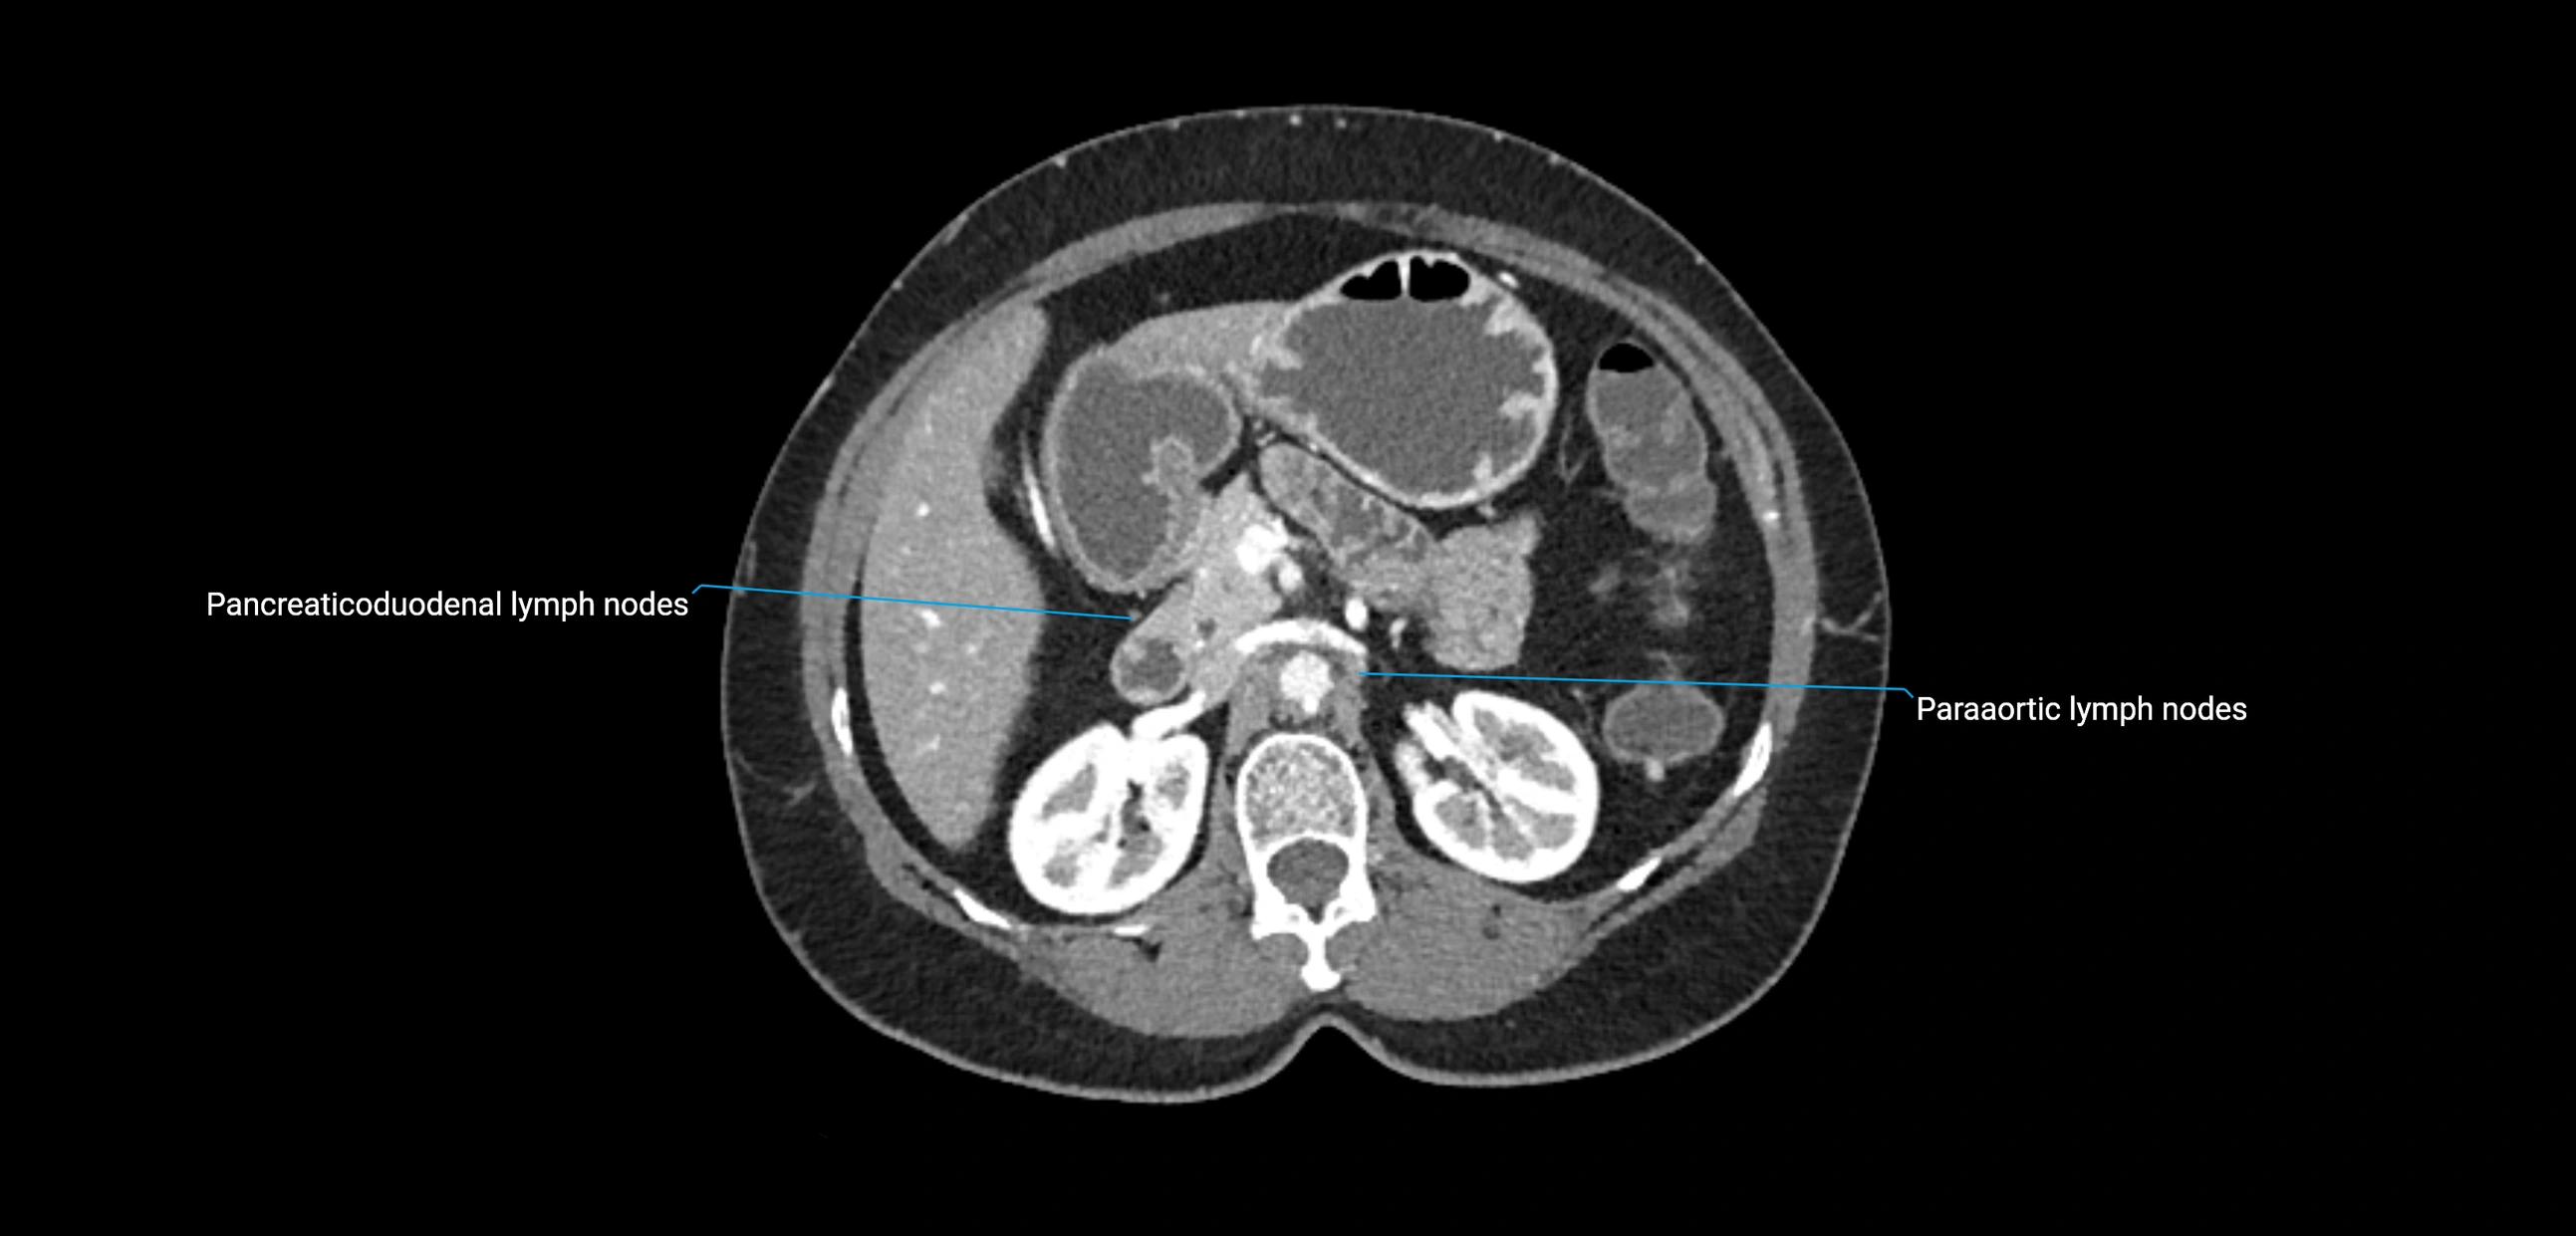

The lateral aortic lymph nodes (also called para-aortic lymph nodes) are a major group of retroperitoneal lymph nodes located along the abdominal aorta and its branches. They lie between the diaphragmatic crura superiorly and the bifurcation of the aorta at L4 inferiorly.

They are positioned on both sides of the abdominal aorta:

• Right lateral aortic nodes: adjacent to the inferior vena cava (IVC)

• Left lateral aortic nodes: lateral to the abdominal aorta

CT Appearance

CT Pre-Contrast:

• Nodes appear as soft-tissue density nodules adjacent to the aorta and IVC

• Calcification may be seen in chronic infections (e.g., tuberculosis)

CT Post-Contrast:

• Normal nodes enhance homogeneously

• Malignant nodes may show heterogeneous enhancement, central necrosis, or conglomerate formation

• Size >1 cm short axis is suspicious, though morphology and distribution are equally important